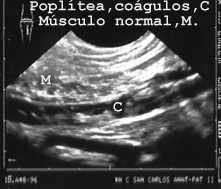

En las extremidades son fáciles de ver los vasos popliteos (Fig 30).

30POPLIT.JPG (20450 bytes)

Fig 30

También se observa en esta imagen el aspecto apolillado típico de los músculos adyacentes. En un corte similar de otro paciente se demostró una trombosis. Además había un absceso muscular (Zona hipoecóica, es decir oscura). La ecopsia localizó el absceso con sencillez y seguridad y su punción dio el diagnostico (Fig 31).